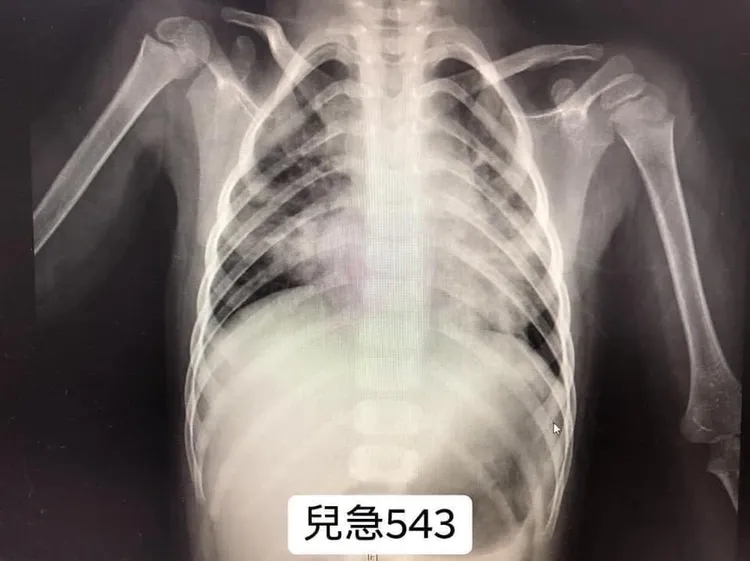

他說,昨天早上一位媽媽帶著小女孩來看急診,這是一名2歲大的女童,Alice。「星期日,Alice開始有咳嗽,今天(星期二)凌晨突然瘋狂般咳嗽,其後併發嘔吐、停止進食,並且出現發燒了。」

女童爸媽遠從新竹帶Alice來兒科急診。媽媽說:「Alice可能感染RSV(呼吸道融合病毒),該病毒正在Alice的幼兒園中傳播!」吳昌騰直言:「真的是如此!RSV似乎正在爆發中!RSV,英文全名是respiratory syncytial virus ,中文名稱『呼吸道融合病毒』。」

吳昌騰說,「大多數孩子在2歲之前的某個時間點會感染RSV。而RSV感染的潛伏期一般為2至8天,通常感染病毒4至6天後出現症狀。」他說,RSV感染的臨床表現不同,症狀可能看起來像普通感冒,視病人年齡及既往健康狀況而定。嬰兒及年紀小的兒童表現為:咳嗽(98%)、發燒(75%)、流鼻涕、喘鳴(65%~78%)、費力呼吸(73%~95%)。它們通常持續一兩個星期,並在適當休息和補充輸液後逐漸好轉。

不過他提醒,「對於一些高危險族群兒童,像是早產兒、慢性肺部疾病或呼吸器依賴、先天性心臟病、先天或後天免疫缺損以及神經肌肉疾病的小孩們,當他們感染RSV時,病情可能會很危險。」輕則導致咳嗽不止、脫水、細支氣管炎或肺炎;重則出現呼吸困難、呼吸衰竭、心肺衰竭等,更嚴重可能還需要插管或使用葉克膜。而預防方式還是戴口罩、勤洗手,可以降低接觸病毒風險。